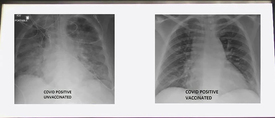

Annak ellenére, hogy az oltás erősíti a védekezőképességet, tény, hogy az oltottak is meg tudnak fertőződni, sőt tovább is adhatják a vírust, tehát a negyedik hullámban újra védekeznünk kell. Viszont sokkal könnyebben és gyorsabban le tudják küzdeni a kórt, akik megkapták mindkét adagot.

A Kaiser Family Foundation (KFF) nevű nonprofit szervezet 24 amerikai állam hivatalos járványadatai alapján részletesebb elemzést készített az áttöréses esetekről. Eszerint az új hullámban az összes fertőzött több mint 90 százaléka került ki az oltatlanok közül, míg a kórházi ápolást igénylő és a halállal végződő eseteknél ugyanez a szám 95 százalék. 900 oltottból egy fertőződött meg Coviddal, 17 ezer közül egyet kellett kórházba szállítani. Halált 83 ezer esetből csupán egyetlen esetben jegyeztek az oltottak között, ami megegyezik azzal, hogy egy amerikai lakos darázscsípésbe haljon bele. Konkrétan egy államot kiragadva: Kaliforniában 992 oltott emberből egy fertőződött meg, míg az oltatlanok esetében 11-ből egy. 22 405 oltott közül egynek volt szüksége kórházi kezelésre, míg 157 oltatlanból egy került kórházba. Az oltottak körében 225 ezer fertőzöttből halt meg egy, miközben az oltatlanok közül minden 486. elhunyt.